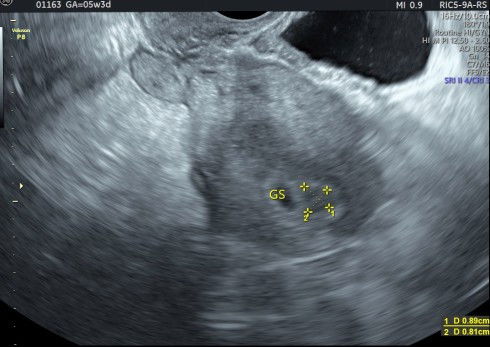

saya hari kamis kemarin usg transvaginal di usia kandungan 5W 3d. hasilnya masih berbentuk kantung saja, dan ada sedikit pendarahan di area kantung kehamilan. saran dokter, untuk bedrest total dan tidak boleh smpai nyeri perut sperti mau mens atau sedang mens🙏